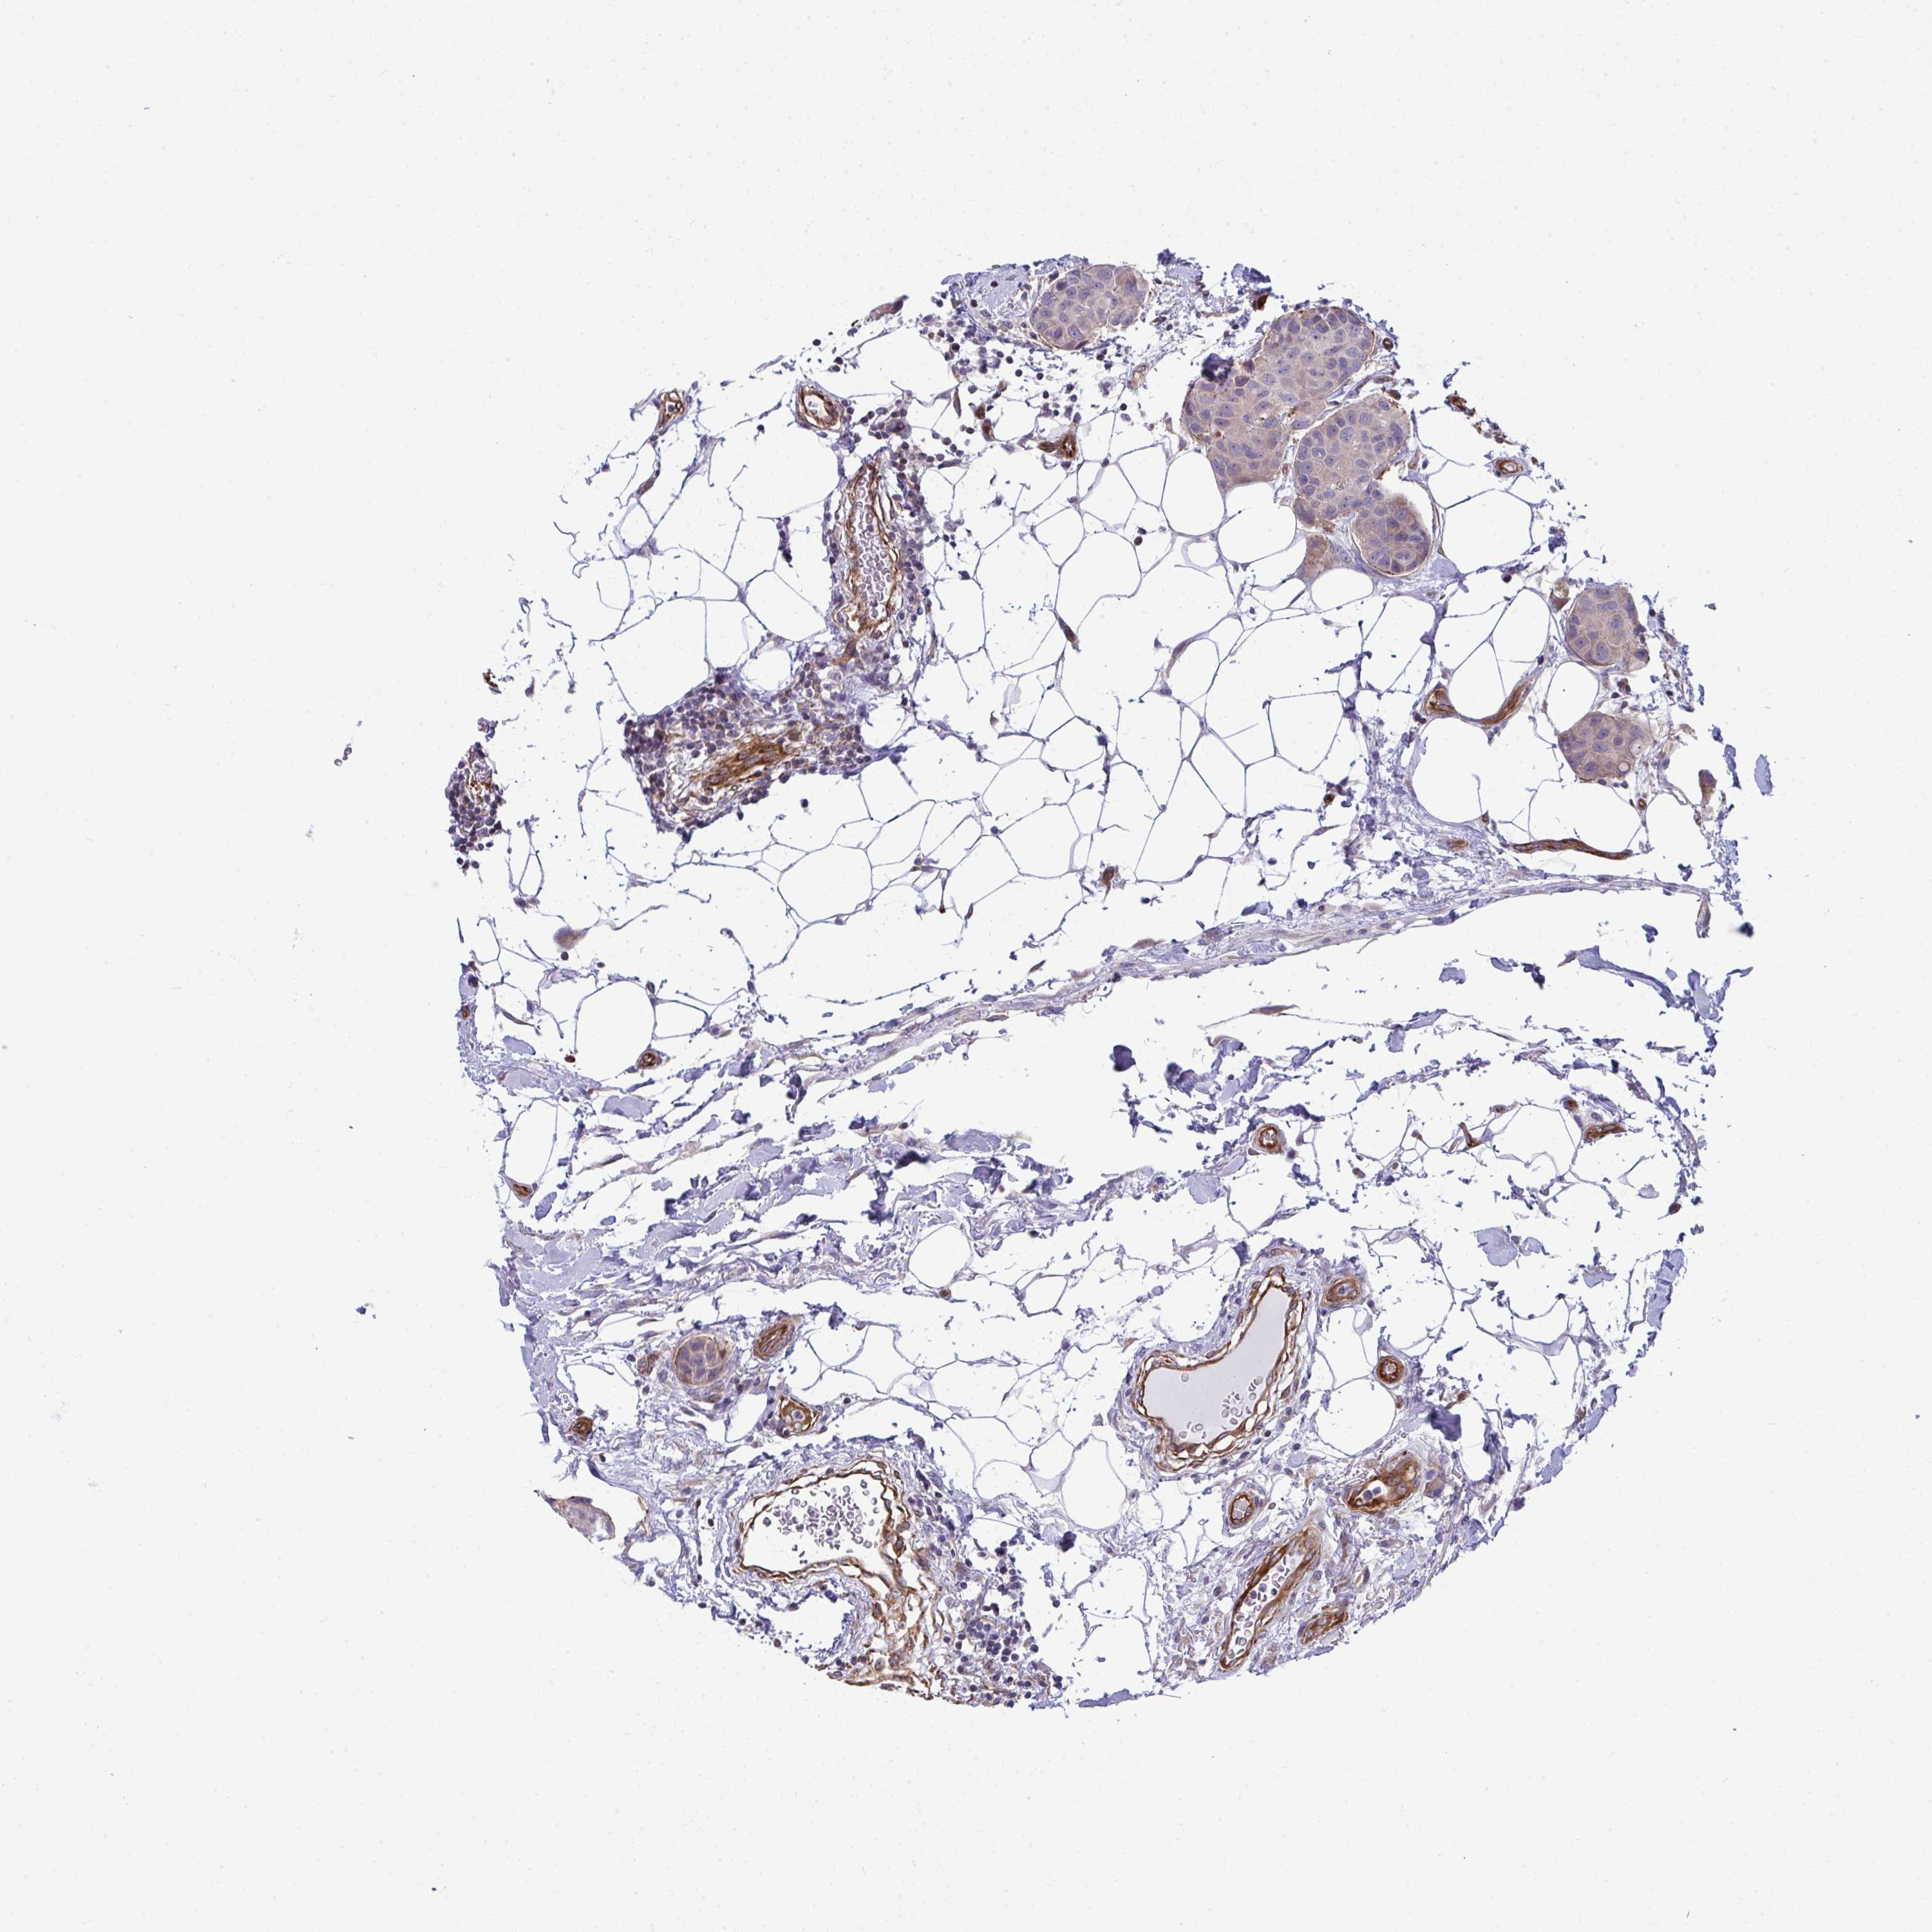

BRCA TCGA BRCA VALIDATION PROTEIN EXPRESSION